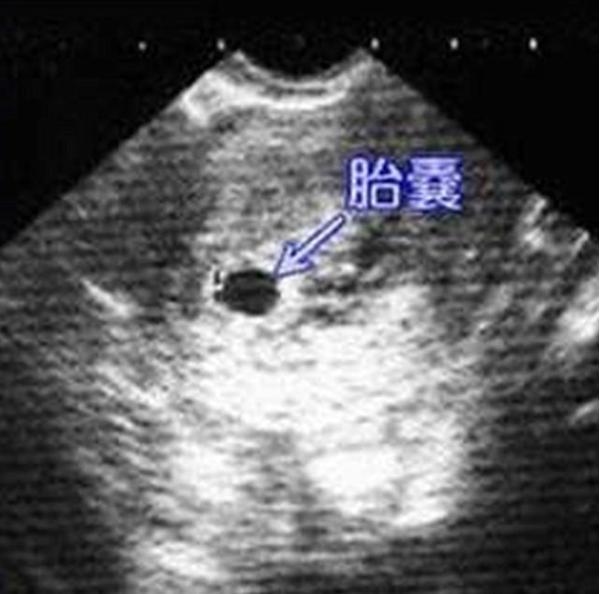

怀孕4周时,受精卵才着床成功; 怀孕5周时,受精卵着床成功后一边快速进行细胞分裂,一边向四周扩展,而这些细胞将会形成羊膜和血管包裹住 卵黄囊,胎儿就是从卵黄囊开始发育的。 在卵黄囊的外面是孕囊,孕囊是原始的胎盘组织。 所以, 一般在怀孕56周,可以做B超看到孕囊和卵黄囊,月经规律的女性,最早在怀孕35天时可以通过阴超看到孕囊; 怀孕67周时,可以通过B超看到胎3 怀孕5周孕囊大小多少是正常的 1、4周:胎儿只有02厘米。 受精卵刚完成着床,羊膜腔才形成,体积很小。 超声还看不清妊娠迹象。 2、5周:胎儿长到04厘米,进入了胚胎期,羊膜腔扩大,原始心血管出现,可有搏动。 B超可看见小胎囊,胎囊约占宫腔不到1胎芽特征 怀孕的第一个月为胎芽期,新生命在此期的成长速度是其一生中最快的。 妊娠第二周末精卵结合,受精后约4天,分裂成细胞团的精卵沿着 输卵管 到达子宫。 第三周,细胞团脱去外膜,为着床作准备。 第四周,胚泡已牢固地植入子宫里。 在这个

4周胎囊-孕囊 4周 02cm 5周 04cm B超孕囊占宫腔不到1/4 6周 085cm B超胎囊清晰可见 7周 133cm 胎囊约占宫腔的l/3 8周 166cm B超可见胎囊约占官腔1/2 9周 215cm B超可见胎囊几乎占满宫腔 10周 2cm 超可见胎囊开始消失 11周 362cm B超可见胎囊完全消失 一般孕周和孕囊大小不用孕妈妈本人进行纠结比较 胎芽一般是在怀孕三十多天以后开始慢慢形成的,通常妊娠三周至妊娠第一个月称为胎芽期,一般孕6—7周B超可见胎芽,大小在051cm左右,胎芽和孕囊大小的对照关系如下: 怀孕周数 孕囊大小 胎芽 4周 孕囊03cm 孕囊体积很小,超声还看不清妊娠迹象 5周